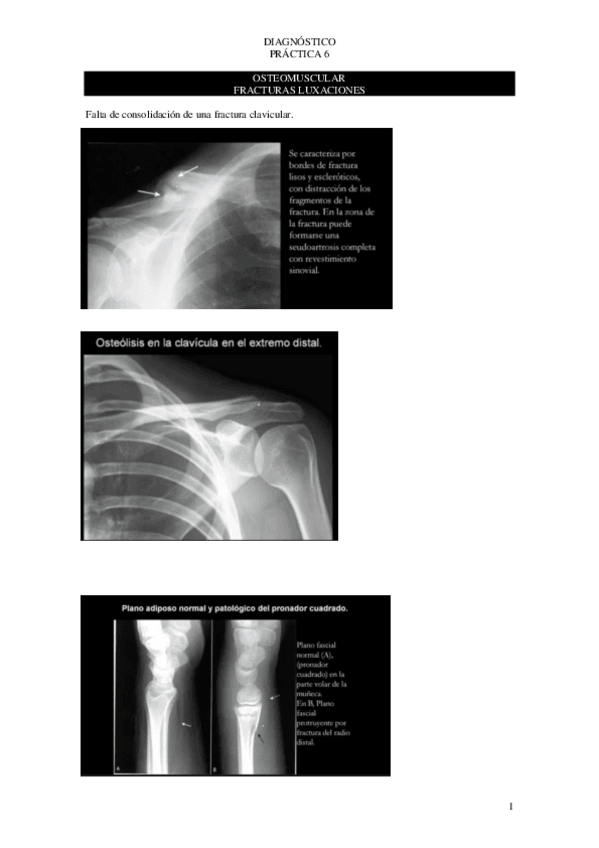

Practica-6-Osteomuscular-fracturas-luxaciones.pdf